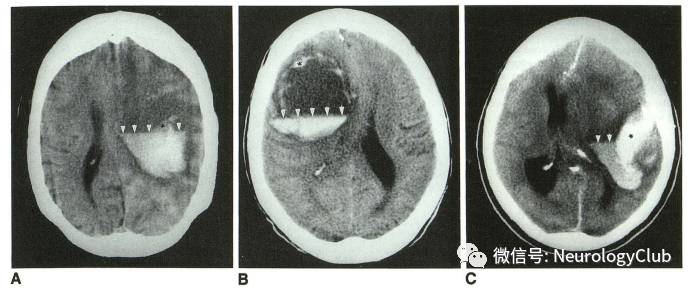

头颅CT是脑出血的首选影像学检查方法约60%的OAT-ICH患者在躺着接受扫描会出现“液平”现象,这是因为无法凝结的血液中血清漂在红细胞之上而产生的 “液平”很少见于凝血功能未受损的患者

(图:头颅CT可见脑出血“液平”现象。引自:Pfleger MJ, Hardee EP, Contant CF Jr, Hayman LA.Sensitivity and specificity of fluid-blood levels for coagulopathy in acute intracerebralhematomas.AJNR Am J Neuroradiol. 1994 Feb;15(2):217-23.